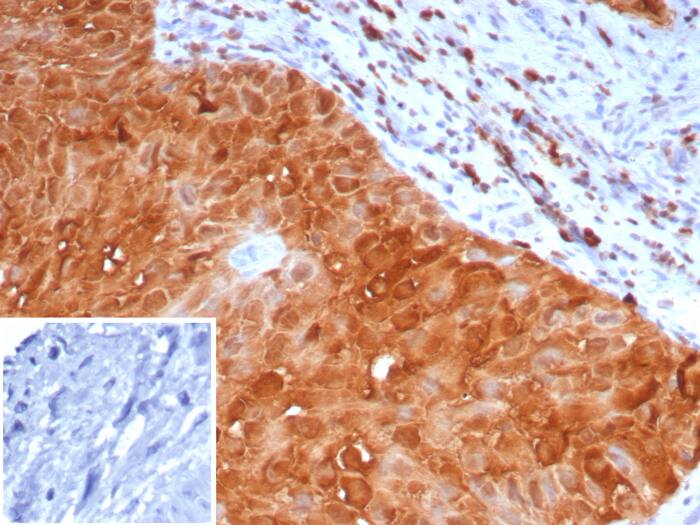

Formalin-fixed, paraffin-embedded human lung cancer stained with S100P Recombinant Mouse Monoclonal Antibody (S100P/7373). HIER: Tris/EDTA, pH9.0, 45min. 2: HRP-polymer, 30min. DAB, 5min.S100P Antibody (S100P/7373) - Azide and BSA Free